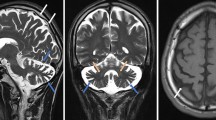

Here, we report four SCAR16 and nine SCA48 patients from two SCAR16 and five SCA48 unrelated French families. All presented with slowly progressive cerebellar ataxia. Additional findings included cognitive decline, dystonia, parkinsonism and swallowing difficulties. The age at onset was highly variable, ranging from 14 to 76 years. Brain MRI showed marked cerebellar atrophy in all patients. Phenotypic findings associated with STUB1 pathogenic variations cover a broad spectrum, ranging from isolated slowly progressive ataxia to severe encephalopathy, and include extrapyramidal features. We described five new pathogenic variations, two previously reported pathogenic variations, and two rare variants of unknown significance in association with STUB1-related disorders. We also report the first pathogenic variation associated with both dominant and recessive forms of inheritance (SCAR16 and SCA48).

Even though differences are observed between the recessive and dominant forms, it appears that a continuum exists between these two entities. While adding new symptoms associated with STUB1 pathogenic variations, we insist on the difficulty of genetic counselling in STUB1-related pathologies. Finally, we underscore the usefulness of DAT-scan as an additional clue for diagnosis.